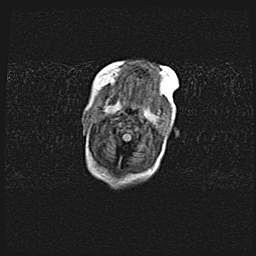

Церебральная ишемия II.

Возраст: 5 дней

Вес: 3400 г

Пол: женский

Окружность головы: 35 см

Срок гестации: 39 недель

Церебральная ишемия – это заболевание, характеризующееся недостаточностью (гипоксией) либо полным прекращением (аноксией) снабжения мозга кислородом по причине закупорки одного или нескольких сосудов. Это приводит к  что метаболическим расстройствам различной степени тяжести в тканях головного мозга, развитию коагуляционных некрозов и гибели нейронов.